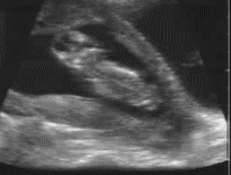

5月7号 .   怀孕第12周4天 .   第三次产检。

这天主要还是要检查所谓的NT值,也就是唐氏综合症。会知道这个东西,其实也是从珊姑娘那里看到。什么也不懂的情况下,就在第一次产检的时候问医生,我什么时候可以检查唐氏综合症?

唐氏綜合症21-三体综合征)又名“先天愚型”,包含一系列的遗传病,其中最具代表性的第21对染色体三体现象,会导致包括学习障碍智力障礙等情況。 在妊娠11~13+6周,测量胎儿颈项透明层厚度(NT检查)是筛查唐氏综合征等染色体异常的敏感指标。62%~80%的先天愚型胎儿可表现出NT增厚(大于3mm)。在妊娠14~16周左右,对羊水进行染色体检查可以明确判明患病与否。这种检查在一般的妇产科医院就能进行。-摘自《wikipedia

所以在这个检查还没做之前,其实我没有一天是过得轻松的,尤其是在医院等待的时候,更是坐立不安。

还好在12周4天做产检的时候,记忆力超好的医生一看到我就说:“所以今天还是决定做检查了?”我猛点头。

医生:“好~现在躺上去,我们来看看你的宝宝今天乖不乖,如果不乖就检查不到了。”我乖乖躺上床。

当医生在做scanning的时候,我们竟然看到我们的宝宝一直上蹿下跳的。我和辉哥惊讶的看着荧幕问医生,“ta…ta在跳吗?”

医生还是用她最灿烂的笑容说:“对亚,其实他一直都在动,只是力气还不大,所以你没有感觉。如果这么早就给你感觉到,那你不是很忙?” LOL

到底宝宝是怎么跳的,我很后悔没有用电话录影下来,因为当下真的太感动了,红了眼眶,压根儿忘了要录影这回事。刚好昨晚在微博看到有人分享,所以下面这个gif图不是我的,只是让大家看看,也是12周的宝宝是怎样在肚子里上蹿下跳的。:)

医生scan肚子的仪器因为宝宝跳动的关系,而一直换姿势。而且一换就说:“ta又换位了” LOL

然后医生又缓缓地吐出:“嗯!你ok!宝宝也很ok!放心好了!”这时候我心里的大石头才真正的卸下。

8个星期大的小不点一下子变大了!从原本的4.8mm到22.8mm。当医生扫描我肚子的时候,我和辉哥不禁惊呼,“才相隔2个星期,就如此不同了!”

上2个星期看到的一小点,两个星期后看到是变大了的小不点,生命实在奇特呀~